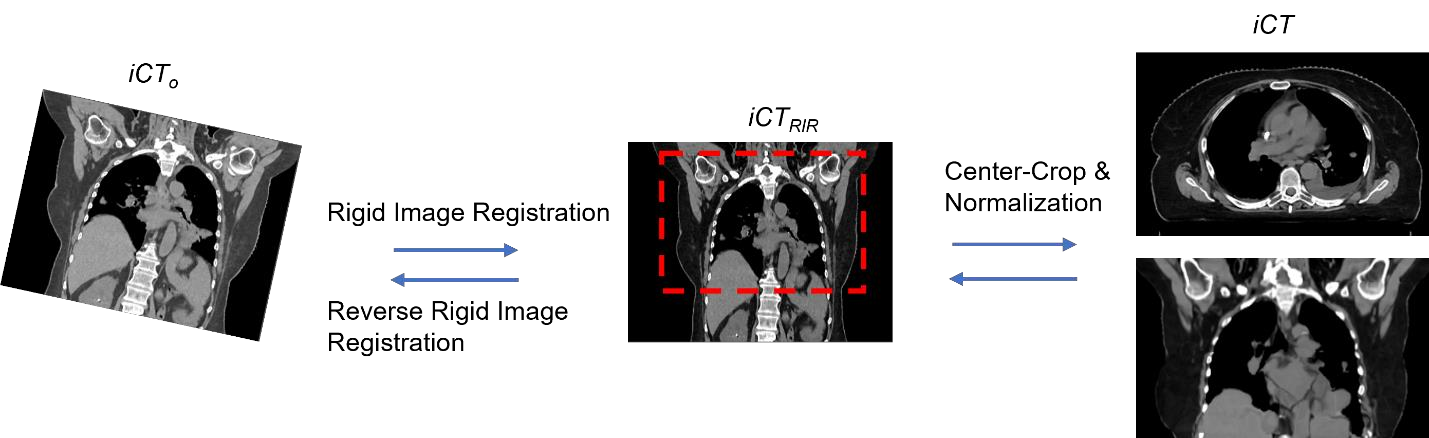

Purpose: In some proton therapy facilities, patient alignment relies on two 2D orthogonal kV images, taken at fixed, oblique angles, as no 3D on-the-bed imaging is available. The visibility of the tumor in kV images is limited since the patient's 3D anatomy is projected onto a 2D plane, especially when the tumor is behind high-density structures such as bones. This can lead to large patient setup errors. A solution is to reconstruct the 3D CT image from the kV images obtained at the treatment isocenter in the treatment position. Methods: An asymmetric autoencoder-like network built with vision-transformer blocks was developed. The data was collected from 1 head and neck patient: 2 orthogonal kV images (1024x1024 voxels), 1 3D CT with padding (512x512x512) acquired from the in-room CT-on-rails before kVs were taken and 2 digitally-reconstructed-radiograph (DRR) images (512x512) based on the CT. We resampled kV images every 8 voxels and DRR and CT every 4 voxels, thus formed a dataset consisting of 262,144 samples, in which the images have a dimension of 128 for each direction. In training, both kV and DRR images were utilized, and the encoder was encouraged to learn the jointed feature map from both kV and DRR images. In testing, only independent kV images were used. The full-size synthetic CT (sCT) was achieved by concatenating the sCTs generated by the model according to their spatial information. The image quality of the synthetic CT (sCT) was evaluated using mean absolute error (MAE) and per-voxel-absolute-CT-number-difference volume histogram (CDVH). Results: The model achieved a speed of 2.1s and a MAE of <40HU. The CDVH showed that <5% of the voxels had a per-voxel-absolute-CT-number-difference larger than 185 HU. Conclusion: A patient-specific vision-transformer-based network was developed and shown to be accurate and efficient to reconstruct 3D CT images from kV images.